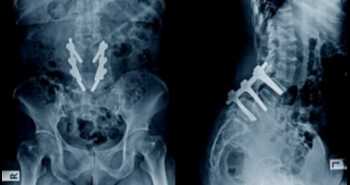

The study cohort included 47 axial spondyloarthritis patients. Individuals were allocated into two arms: (I) Group A was administered caudal epidural injections, ultrasound-guided, with 1% lidocaine hydrochloride mixed with triamcinolone (ii) Group B was not given any injections. All the subjects fulfilled the Assessment of Spondyloarthritis International Society (ASAS) criteria for axial spondyloarthritis.

The outcome parameters were: (i) visual analogue scale, (ii) lateral lumbar flexion, (iii) modified Schober test, (iv) Oswestry disability index (ODI), and (v) Ankylosing Spondylitis Disease Activity Score (ASDAS) with an evaluation at baseline, two and eight weeks after therapy.

A substantial difference was noted between both the groups regarding spine mobility, pain, ODI, and ASDAS scores in favor of group A. This impact was at its maximum after two weeks. Despite the decrease in this effect after two months, the difference between the arms remained substantial. Young age, elevated disease activity, and a shorter duration of disease were linked with improved outcomes.